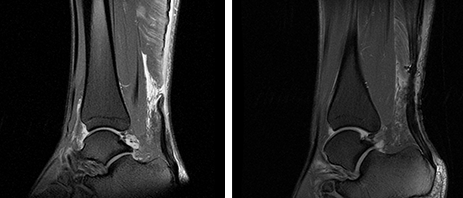

자기공명영상 검사 (MRI)

가장 자세한 검사법으로 아킬레스건 파열의 정도 및 파열단 사이의 벌어진 틈을 정확하게 파악이 가능합니다.